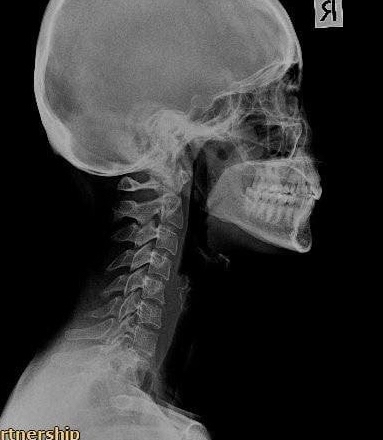

พนักงานออฟฟิศ (Case 3)

อาการ: ออฟฟิศซินโดรม / กระดูกคอตรง

"จากการนั่งทำงานหน้าคอมพิวเตอร์เป็นเวลานาน ทำให้กระดูกคอเสียความโค้ง หลังรับการฟื้นฟู สรีระคอดีขึ้น อาการปวดบ่าร้าวขึ้นศีรษะลดลงอย่างเห็นได้ชัด"

Before

After